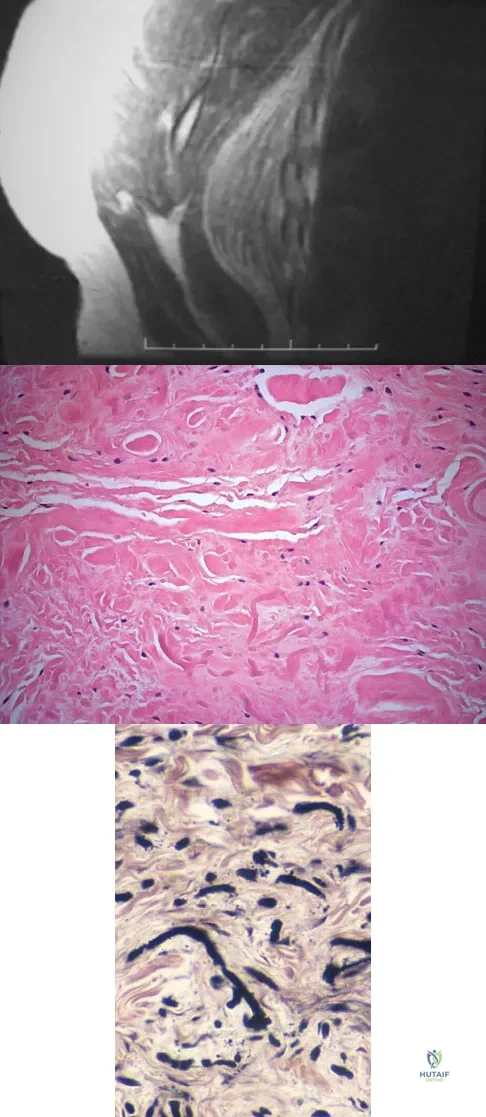

A 73-year-old man stepped off a street curb and felt a crack in his left hip. He is now unable to bear weight. A radiograph is shown in Figure 54a. Biopsy specimens are shown in Figures 54b and 54c. What is the most likely diagnosis?

Explanation